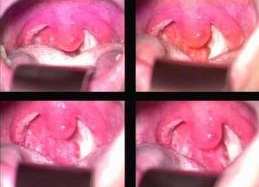

Khi cho trẻ ăn thạch đặc biệt là trẻ dưới 5 tuổi các bậc cha mẹ phải để ý cẩn thận và cắt nhỏ ra trước khi cho trẻ ăn. Trong trường hợp trẻ bị hóc thạch chúng ta đưa ngay đến bác...